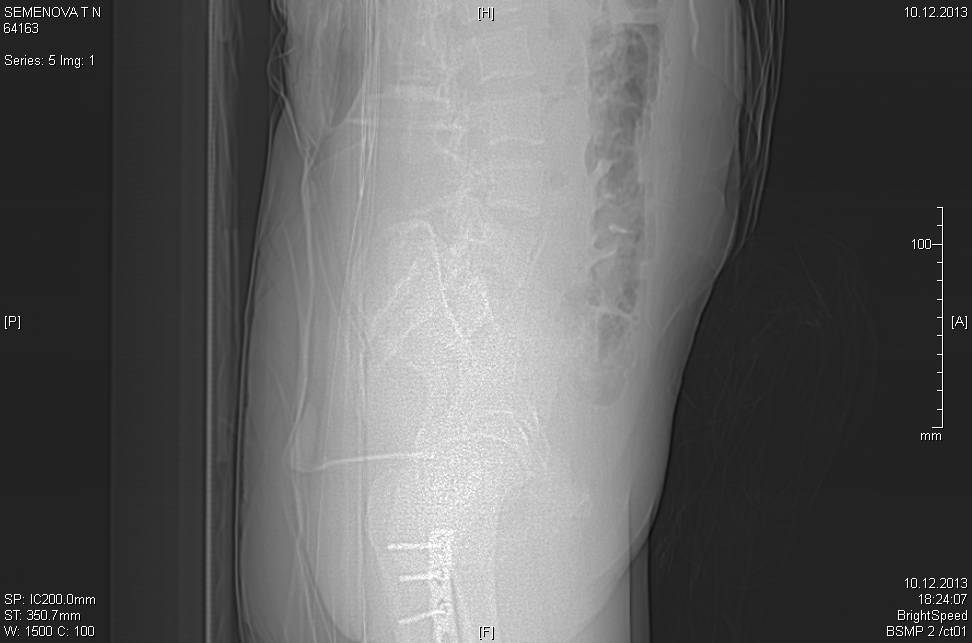

Доброго времени суток коллеги! Прошу вас, подсказать тактику в решении

оперативного лечения следующего сложного повреждения таза. Был ли опыт в

фиксации подобных повреждений?

Травма 03.12.2013,больная переведена из лечебного учреждения соседней

области. На данный момент у больной следующий диагноз: ЗЧМТ,сотрясение

головного мозга;Закр. травма грудной клетки,множественные переломы ребер

справа с повреждением ткани легкого, правосторонний гемопневмоторакс,

состояние после торакоцентеза; Закр.травма живота,разрыв

селезенки,гемоперионеум, состояние после лапаротомиии спленэктомии;

Закр. оскольчатый перелом сред-верх\3 левой бедренной кости, состояние

после накостного металлостеосинтеза; Закр.поперечный переломовывих на

уровне S1S2, многооскольчатый перелом латеральных масс крестца с обеих

сторон,перелом обеих лонных и седалищных костей.

Перелом поперечных отростков L1,L2,L3,L4, L5 позвонка справа. ШОК 3ст.

Вкратце изложил диагноз.

В настоящее время состояние больной тяжелое. Первым этапом планируем

наложить АНФ (переднюю раму) После стабилизации состояния необходимо

будет выполнить фиксацию.

Имеется один вопрос - какие импланты необходимы т.е. в какой комбинации

и какая последовательность фиксации?